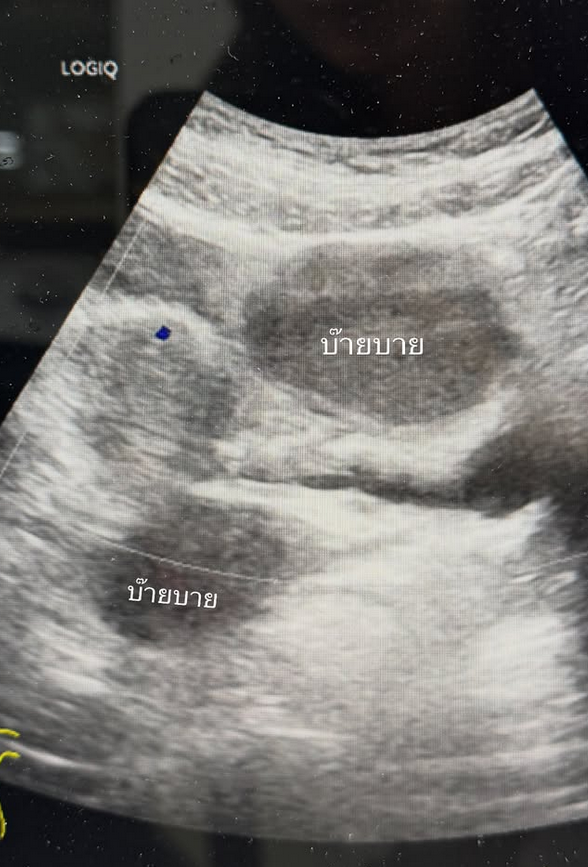

ทำเอาแฟนๆต่างส่งกำลังใจให้กันอย่างล้นหลามสำหรับนักแสดงสาว จ๊ะจ๋า พริมรตา เดชอุดม เมื่อได้ออกมาโพสต์ภาพตนเองขณะเตรียมตัวเข้ารับการผ่าตัดว่า บ๊ายบายน้องช็อกโกแลต ขอให้เราไม่ต้องเจอกันอีกนะน้องเป็นถุงน้ำรังไข่ที่เกิดจากเยื่อบุโพรงมดลูกเจริญผิดที่ ซึ่งถุงน้ำของจ๋ามีขนาดใหญ่เกินกว่าที่จะกินยาให้เค้ายุบได้